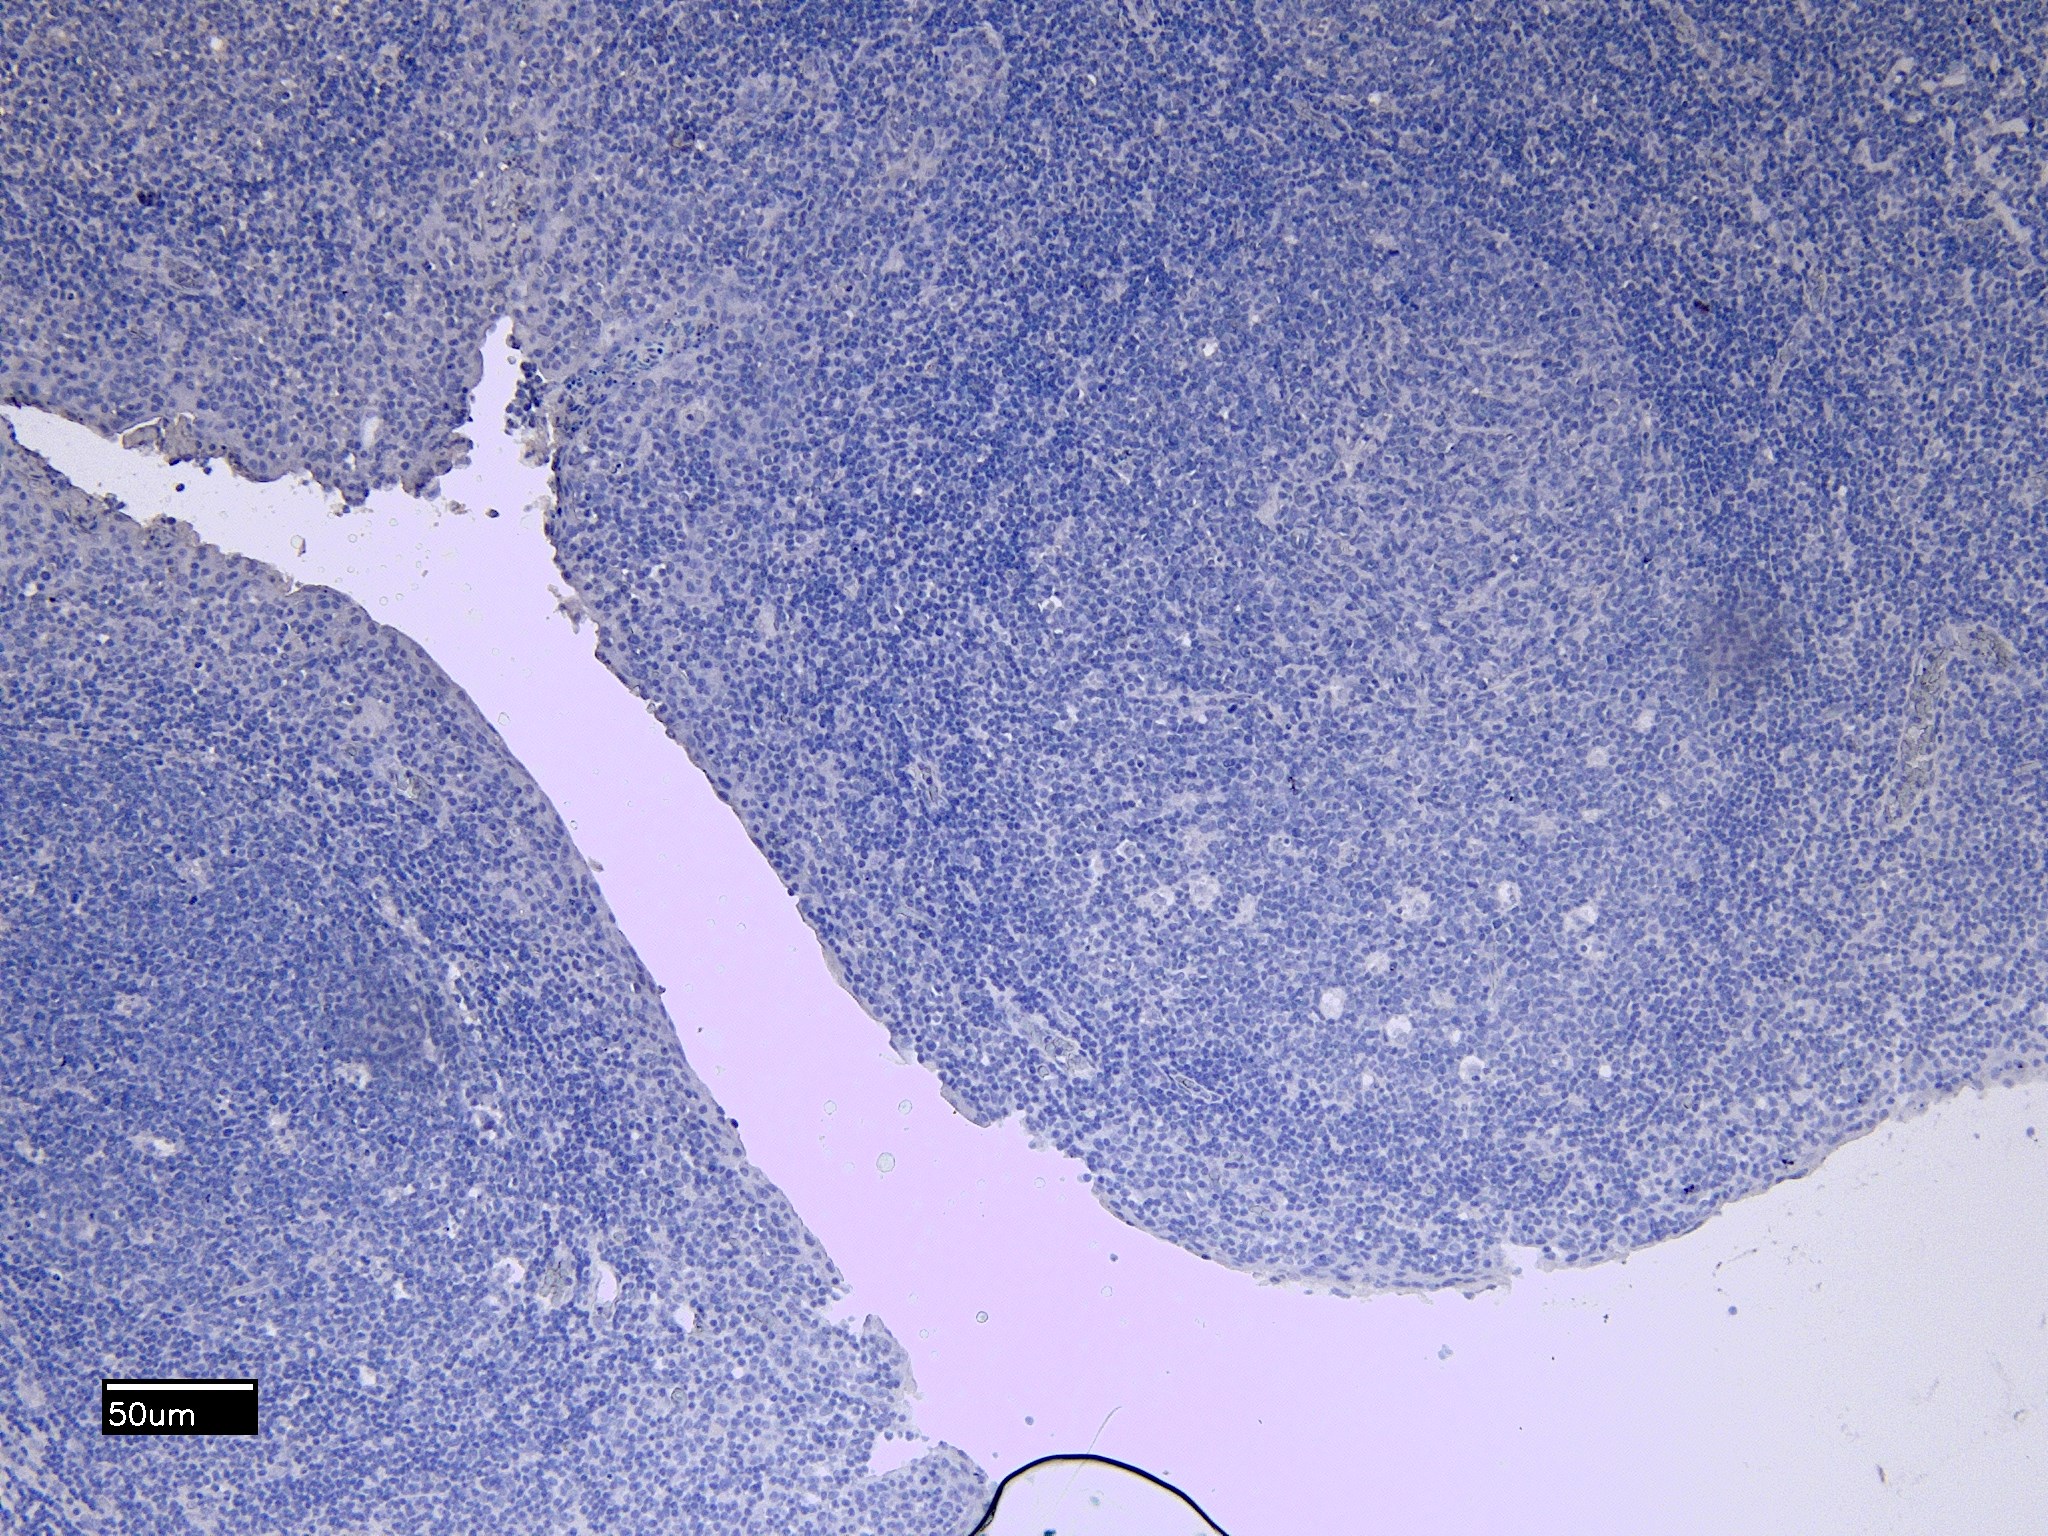

IHC Results Paraffin embedded Human Tonsil. Recommended concentration: 6-8µg/ml. | |